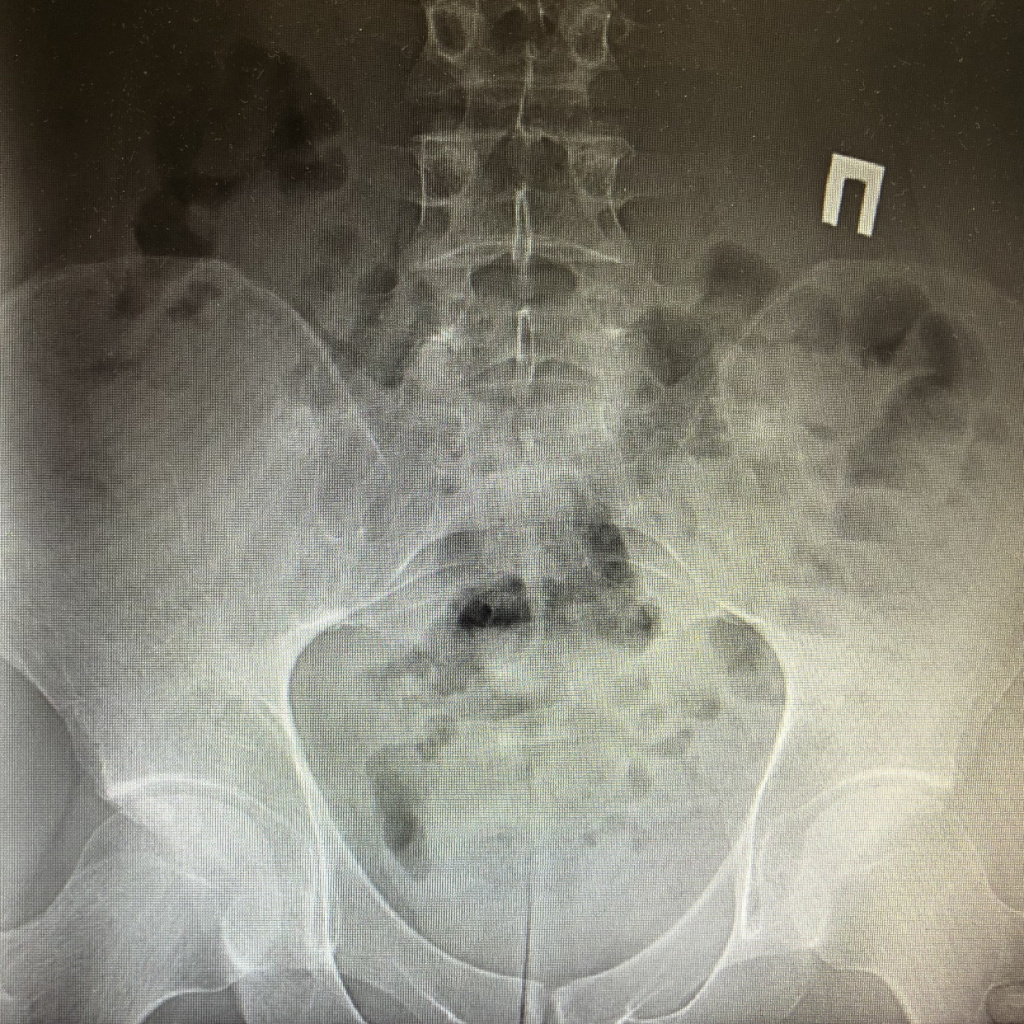

Боль в нижней части спины

В терапевтической практике самой распространённой жалобой пациентов является боль в различных отделах спины. Глобально, данную боль необходимо разделить на механическую и воспалительную.

В свою очередь боль воспалительного характера (в превалирующем большинстве в пояснично-крестцовом отделе позвоночника) имеет противоположные характеристики, а именно: начало возникновение боли ранее 40 лет (преимущественно в 20-30 лет), возникновение болевого синдрома растянуто во времени (в течение не менее 3-6 месяцев), снижение качества жизни пациентов связано с тем, что максимальные проявления боли приходятся на вторую половину ночи и ранее утро.

Как правило, пациенты часто просыпаются среди ночи, а утром присутствует «скованность» (т.е. тугоподвижность) в затронутом отделе позвоночника. В свою очередь, в отличие от механической боли, физические упражнения (например, ЛФК, плавание) или использование горячего душа, уменьшают проявления боли и скованности. Боль воспалительного характера наблюдается при заболеваниях из группы воспалительных спордилоартропатий (аксиальный спондилоартрит, анкилозирующий спондилит (болезнь Бехтерева), псориатический спондилит, спондилоартрит, ассоциированный с воспалительными заболеваниями кишечника (болезнь Крона, неспецифический язвенный колит (НЯК)), реактивные артриты).